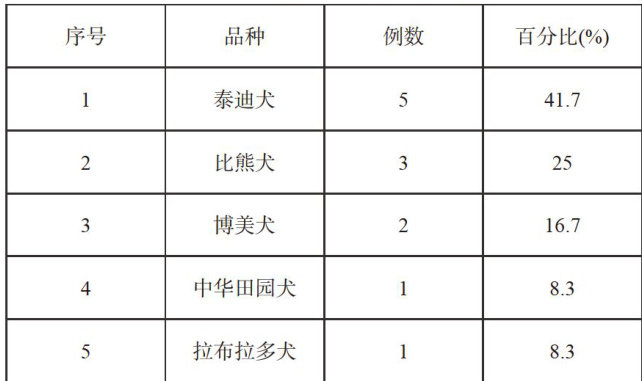

实践案例 | 楚雄地区犬服用人用布洛芬中毒案例浅析

实践案例 | 楚雄地区犬服用人用布洛芬中毒案例浅析